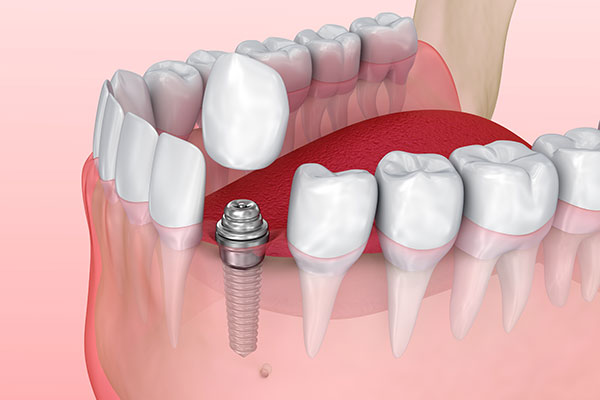

インプラント治療は、失った歯を補うために人工の歯根(歯の根っこ)をあごの骨に埋め込む治療法です。インプラント体は通常チタンでできており、チタンが骨と結合する性質があることから、強固で安定した基盤が作られ、その上にアバットメント(土台)を接続し、上部構造(人工歯)を装着します。これにより、見た目も自然で、機能的にも快適な歯を再建することができます。インプラントは自分の歯とほぼ同じように感じられ、他の歯への負担も最小限に抑えられます。

インプラントの埋入手術

治療計画に基づいて、インプラントをあごの骨に埋め込む手術を行います。手術は局所麻酔で行い、痛みを感じにくいようにします。手術後、インプラントがあごの骨としっかり結合するまで、数ヶ月の治癒期間を設けます。

人工歯の製作と取り付け

アバットメントが取り付けられた後、患者さまのお口の状態に最適な人工歯を製作します。歯の色や形、かみ合わせを患者さまの希望に合わせて調整し、最終的に人工歯をアバットメントに取り付けてインプラント治療は完了です。